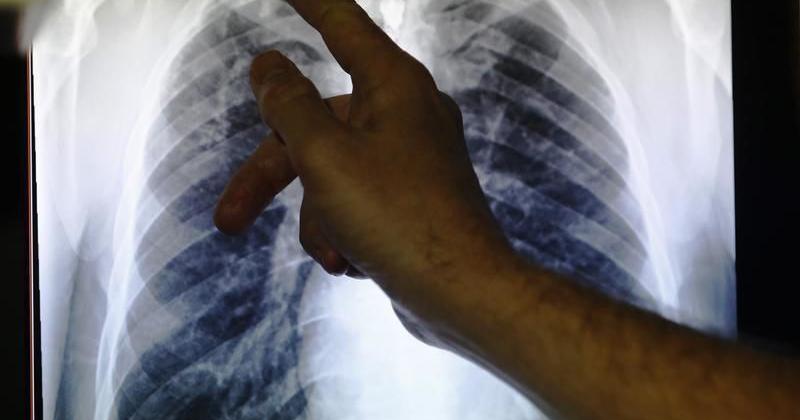

Two more people infected with tuberculosis were identified in Manchester and Nashua recently, state health officials announced Wednesday.

The two infected people are the second and third diagnosed with active tuberculosis (TB) in the Manchester and Nashua areas since March , according to a press release from the New Hampshire Department of Health and Human Services.